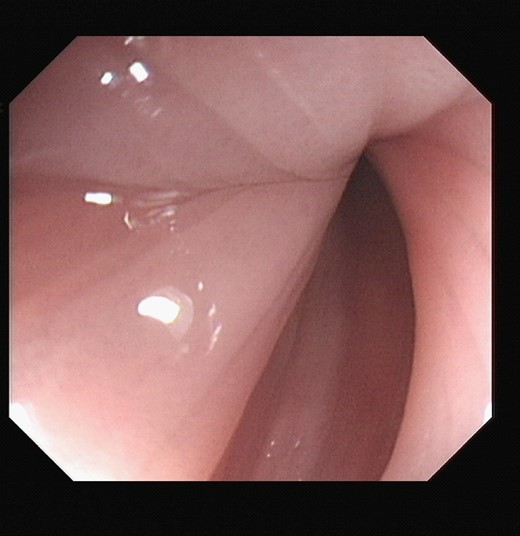

Unfortunately on the fifth day of Mr. X’s admission, he became acutely unwell with left iliac fossa pain and vomiting. Repeat sigmoidoscopy revealed a blue mucosa which appeared ischaemic with no visible peristalsis. Attempted decompression was unsuccessful, Fig. 5.

Repeat sigmoidoscopy: bluish discolouration of mucosa concerning for ischaemia.